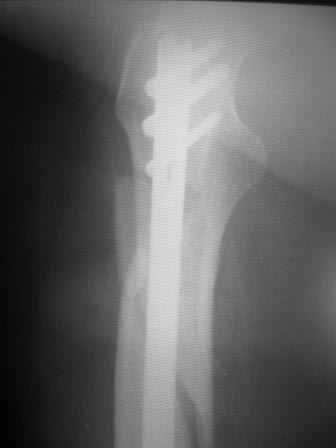

АЖ> Дык и я о том же! Не о репозиции перелома, а о введении штифта в

При многооскольчатых переломах стержень может "выпасть" кзади под весом кондуктора и своим, даже если поначалу он вводился правильно. Чтобы эту неприятность предупредить, стоит ввести спицу по оси шейки бедра вдоль ее задней стенки, типа как на картинке. Если стержень кпереди от этой спицы вводить, то он за нее не провалится.